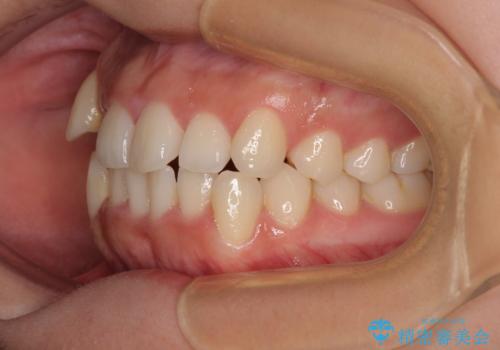

- 上下前歯のデコボコを気にして来院された患者様です。

上顎歯列が下顎の歯列に対して狭小であり、一部下顎の奥歯が上顎よりも外側に位置している状態でした。